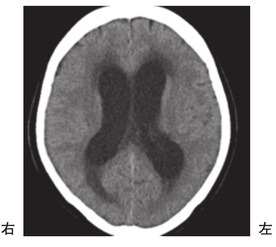

脳梗塞の発生部位によって出現する症状は異なります。この問題では、それぞれの部位における症状を正確に理解することが求められています。

左放線冠は部位によって様々な症状が現れますが、感覚性失語はWernicke領域で見られるため、この選択肢は誤りです。